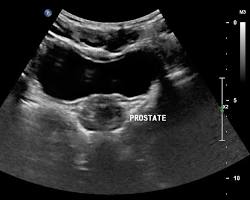

- To assess the prostate gland: This is usually done as part of a prostate cancer screening or to investigate symptoms such as difficulty urinating.